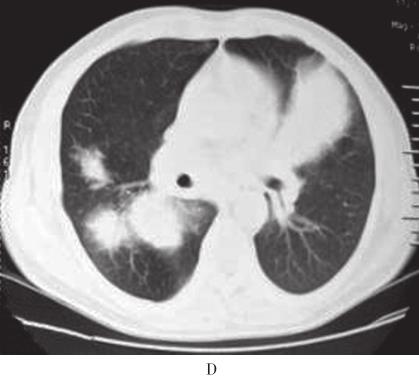

患者,男,56岁,因“活动后气短4年,加重3周”于2010年10月12日入院。入院前4年无诱因出现活动后气短,吸气时明显。3年前当地医院胸部CT检查示:双肺野内多个大小不等团片状密度增高影(图1A、B)。支气管镜下见:左上叶开口、右上叶开口及右下叶基底段开口处黏膜充血肿胀,管腔狭窄。支气管镜活检病理显示有大量淋巴细胞浸润。抗感染治疗后症状稍缓解。入院前1年上述症状加重,胸部CT示:双肺多发结节状、团块状病灶(图1C、D)。CT引导下肺穿刺活检病理示有大量淋巴细胞及浆细胞浸润,血管扩张充血,炎性渗出。诊断为双肺多发炎性肉芽肿,具体治疗不详。入院前2个月出现反复右侧鼻腔少量出血。入院前3周活动后气短加重,拟诊“双肺多发阴影性质待查”收入院。病来无发热、盗汗、咯血、胸痛、皮疹、关节痛。患者4年间多次在当地医院就诊,“怀疑肺结核、肺真菌病及肉芽肿病”,经验采用抗结核、抗真菌等治疗,具体治疗方案及疗程患者及家属叙述不清,疗效不佳。入院前半年,出现乏力、食欲下降,体重减轻4~5kg。

图1 胸部CT

A、B:2007年4月胸部CT示双肺野内多个大小不等团片状高密度.C、D:2009年10月胸部CT示双肺多发结节样、团块样病.E~G:2010年10月胸部CT示右肺下叶巨大团块状类软组织密度影,双肺弥漫性团片状浸润及实变影,纵隔内多发肿大淋巴结;胸片示右下肺团块影,双肺多发结节影